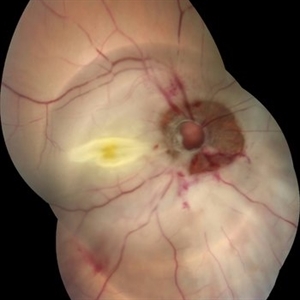

Post Traumatic Optic Nerve Head Avulsion

Nov 18 2017 by Vishal Agrawal, MD, FRCS,FACS,FASRS

Right eye fundus picture of a 24-year-old male patient who suffered blunt trauma 7 days back with a wooden stick . He presented with NLP vision with a non reacting dilated pupil. Fundus montage picture shows ONH avulsion,CRAO,peripapillary resolving hemorrhages and cicatricial tissue at the edge.

Photographer: Vishal Agrawal, MD, SMS Medical College, Jaipur, India

Imaging device: Zeiss 524

Condition/keywords: avulsion, central retinal artery occlusion (CRAO)